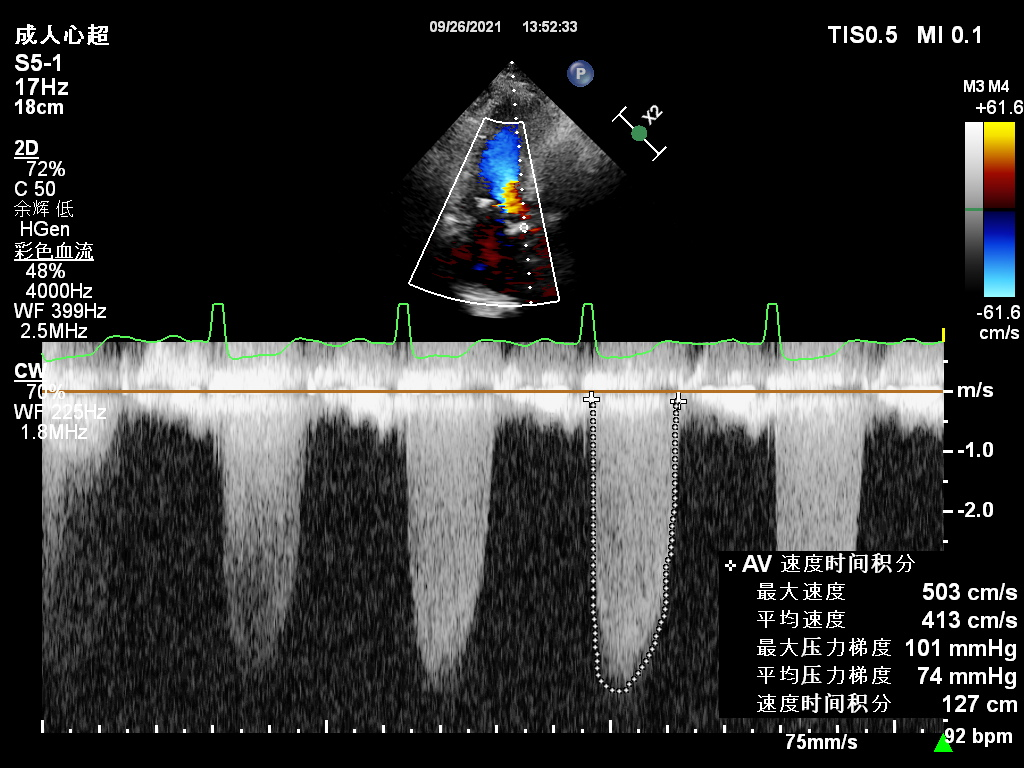

术后超声

主动脉瓣最大流速由5.03 m/s下降至1.36 m/s,平均压差由74mmHg下降至4mmHg,未见主动脉瓣反流